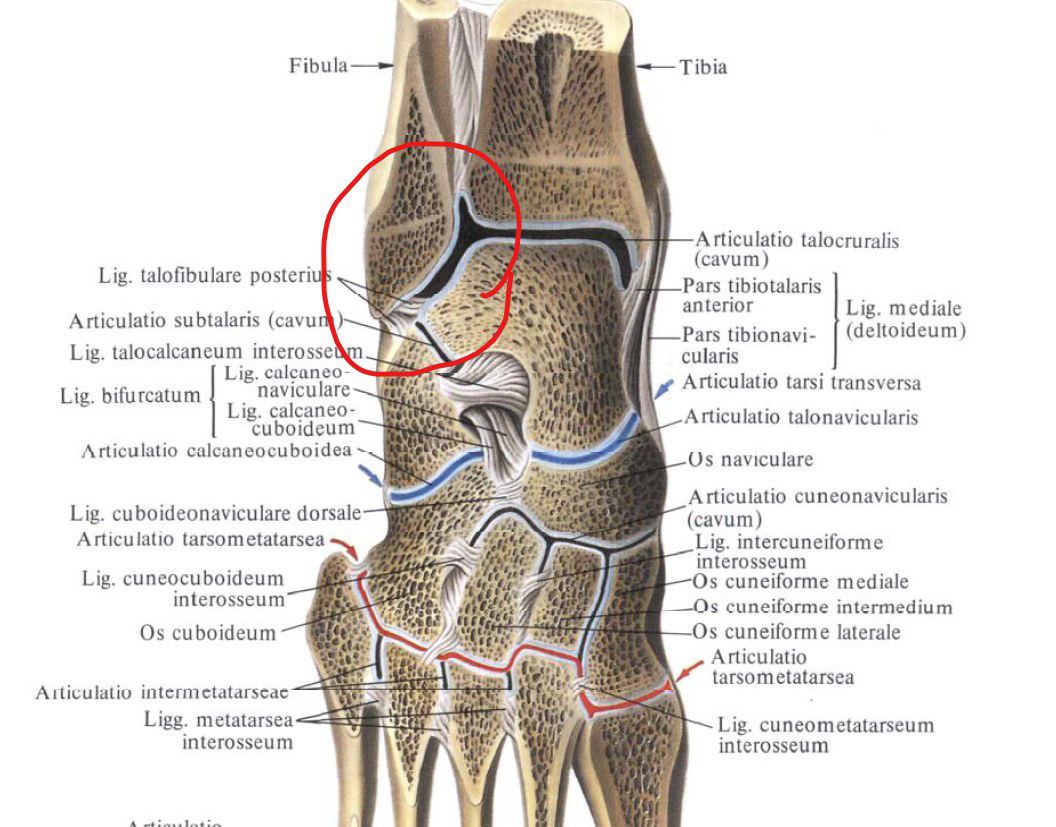

Анатомические фото голеностопного сустава и его суставных поверхностей